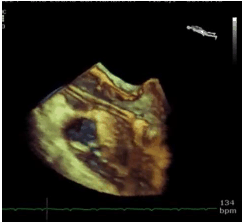

Identifique o nome do dispositivo protético presente na foto abaixo.